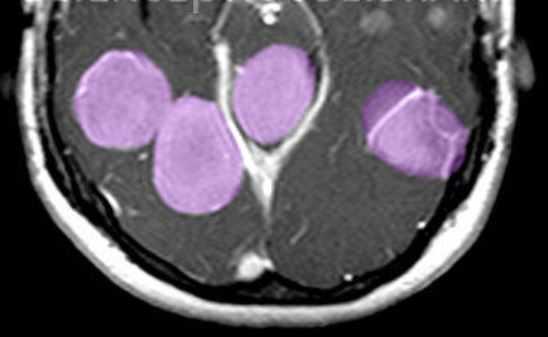

МРТ головного мозга. Т1-взвешенная МРТ с контрастированием. Множественные менингиомы при нейрофиброматозе 2 типа. Цветовая обработка изображения.

Нейрофиброматоз II типа также имеет аутосомно-доминантный тип наследования, но сцепленный с 22 парой хромосом. Его частота составляет один на 100 тыс. населения. Диагностическими критериями служат (National Institutes of Health, 1988) двухсторонние невриномы слуховых нервов, выявляемые на КТ или МРТ, либо сочетание наследственной предрасположенности (наличие двухсторонних неврином у ближайшего родственника) с односторонней невриномой или двумя другими типичными опухолями (плексиформная нейрофиброма, менингиома, глиома, невринома любой локализации) плюс кожные пятна. В отличие от НФ I кожные пятна единичные и не служат главным критерием, а опухолевое поражение ассоциируется не с астроцитомами, а с невриномами и менингиомама. Сопутствующими патологиями являются менингоангиоматоз, глиальные узлы, эпендимальные эктопии, гипертрофический глиоз зрительного нерва, сирингомиелия, комплекс Арнольда-Киари. Типичная невринома развивается из шванновской оболочки слуховых нервов (VIII пара), обычно с обеих сторон , реже тройничного нерва или других. При МРТ невриномы гипо- или изоинтенсивны белому веществу на Т1-взвешенных МРТ и изо- или гиперинтенсивны на Т2-взвешенных МРТ. Хорошо усиливаются гадолинием. Менингиомы, как правило, сопутствуют невриномам. Локализация не отличается от случаев не связанных с нейрофиброматозом, но встречается также нетипичное поражение сосудистого сплетения. Картина менингиом при нейрофиброматозе II типа имеет все типичные признаки.